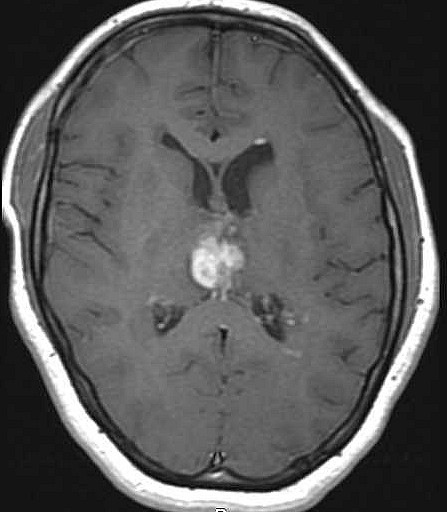

| Fem. 17a. |

| Nódulo sólido homogêneo preenchendo o III ventrículo, com limites precisos, com hipossinal em T1 e hipersinal em T2 e FLAIR, que se impregna por contraste paramagnético. Lesão menor implantada no assoalho do IV ventrículo provavelmente representa disseminação por via liquórica. |

| CORTES AXIAIS, T1 COM CONTRASTE | ||

| F. 17a. Tumor teratóide rabdóide atípico de III ventrículo. RM | HE | VIM, GFAP | HHF35, desmina, 1A4 | AE1AE3, EMA |